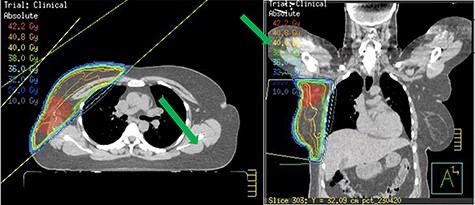

Staging bone and CT scan showed no evidence of distant metastasis. She underwent Oncotype DX test for risk stratification and consideration of chemotherapy. The Oncotype DX recurrence score was 15 with group average absolute chemotherapy benefit <1%. Following careful consideration and discussion, chemotherapy was avoided. The patient received 4 weeks of forward-planned IMRT adjuvant radiotherapy to the right breast along with boost to the tumour bed (Fig. 4). She was commenced on tamoxifen due to her perimenopausal status.

Controversy exists regarding surgery. Earlier reports recommended ipsilateral mastectomy whereas more recent reports suggest there is no additional advantage with mastectomy over total excision of accessory breast tissue [4, 6]. Total excision of accessory breast tissue including cancer and sentinel node biopsy is recommended. Axillary clearance is performed if preoperative lymph node biopsy is positive. Mastectomy is not required if there is no lesion noted within the anatomical breast on triple assessment. Our patient had no abnormality within the anatomical breast on examination and mammogram. Further adjuvant treatment namely chemotherapy, radiotherapy and endocrine treatment depends on the histology result and oncotype DX score. In our patient, Oncotype DX results did not show significant benefit of chemotherapy, hence this was avoided. As she was young and had T3 tumour we offered her adjuvant radiotherapy along with boost to the axillary tumour bed to reduce local recurrence. She was also recommended endocrine treatment.